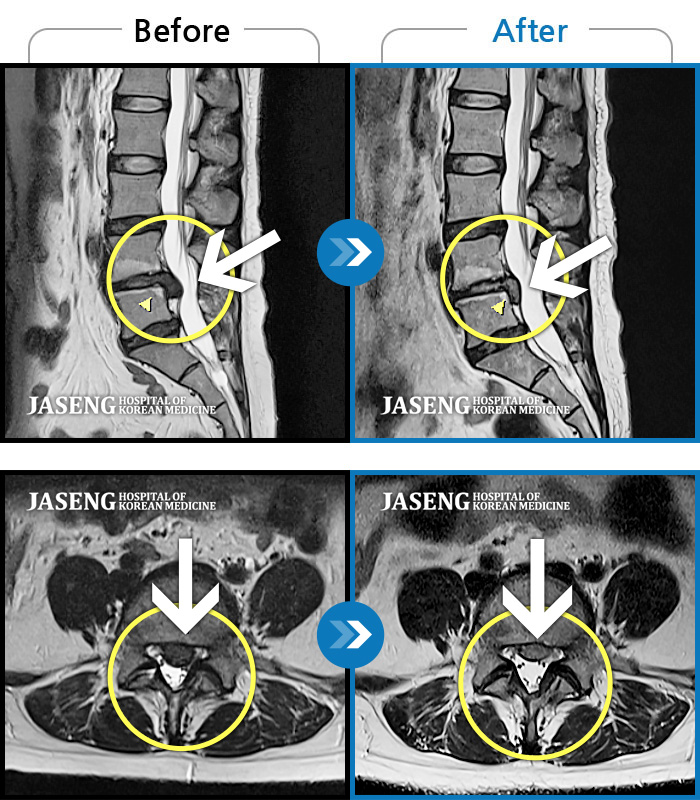

허리디스크

광주 · 장영우 원장

양측 허리부터 골반 묵직한 통증, 좌측 다리 외측까지 이어지는 당기는 통증으로 내원하셨습니다.

촬영시기

2503.04.01 ~ 2509.11.01

2025.09.22